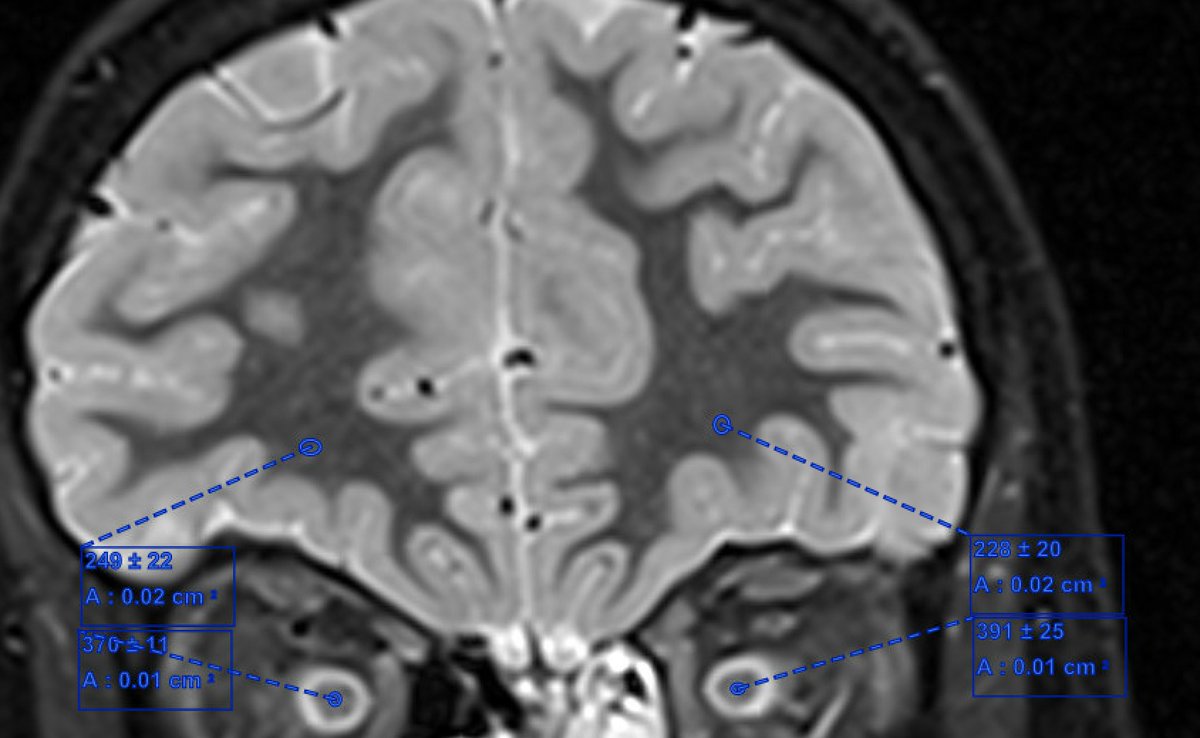

I’m not nice so I won’t tell you the eye exam but here is the MRI. Describe what you see… #childneurology

If you are having a rough time deciding whether or not the optic nerves are enhancing, you're not alone. @Dr.GlenTung always reminds us to use the coronal T2 with fat suppression to evaluate for optic nerve edema...@daniel_gewolb agree?